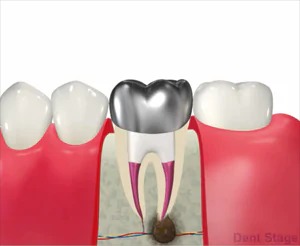

むし歯を繰り返すと、最終的には神経を取って「根管治療(歯の根の治療)」を行う必要が出てきます。根管治療が適切に行われれば、ご自身の歯を残すことができます。しかし、治療の際に細菌が残ってしまうと、根の先に膿がたまり、再治療が必要になる場合があります。

再治療を繰り返すほど歯を失うリスクが高くなります。

根管治療は歯を抜かずに残すための、とても大切な最終段階の治療です。

再根管治療の場合

まず初めに被せ物、土台、根管充填物をなるべく歯を残しながら除去します。

再根管治療の場合は、すでに根管内が汚染され、尚且つ不適切な根管治療が行われていることが多いので、治療としては、抜髄よりも治療回数も増え、成功率が下がります。